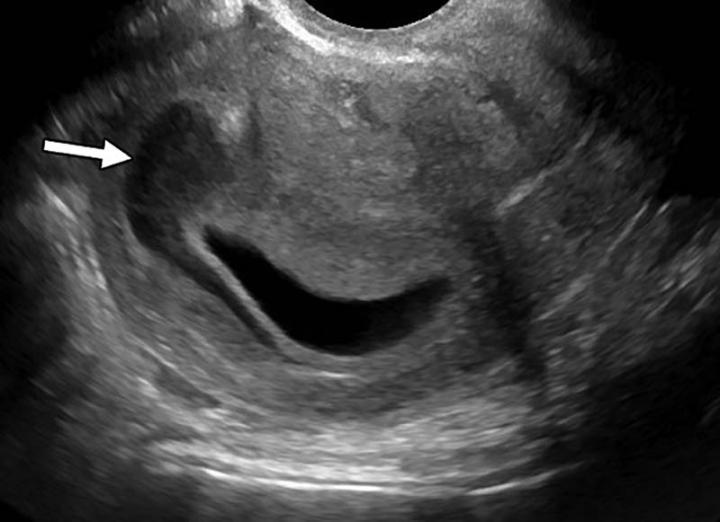

The researchers found that almost all of the intimate partner violence victims were women (96 percent). Victims had a mean age of 34.2 years. Thirty-seven percent were African-American and 28 percent were Hispanic. Victims of intimate partner violence, on average, underwent approximately four times more imaging exams in the preceding five years compared to the control group. Acute fractures and obstetric/gynecologic findings, such as pregnancy loss and intrauterine growth restriction, were associated with two to four times higher odds of domestic violence.

"Our study suggests that these otherwise common findings could be indicative of intimate partner violence in the setting of specific socioeconomic factors identified in our study," said study first author Elizabeth George, M.D., chief resident in the Department of Radiology at Brigham and Women's Hospital and clinical fellow at Harvard Medical School.